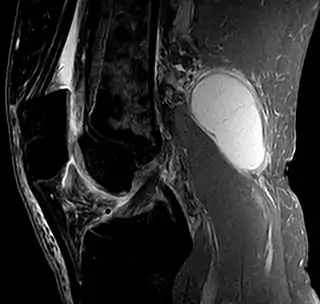

![]() Quiste de Baker, en una imagen sagital obtenida por resonancia magnética. | ||

El diagnóstico se realiza mediante examen. Un quiste de Baker es más fácil de ver desde atrás cuando el paciente está de pie con las rodillas completamente extendidas. Se palpa (siente) más fácilmente con la rodilla parcialmente flexionada. El diagnóstico se confirma mediante ecografía, aunque si es necesario y no hay sospecha de un aneurisma de la arteria poplítea, se puede realizar con cuidado la aspiración del líquido sinovial del quiste. Una imagen de resonancia magnética puede revelar la presencia de un quiste de Baker.